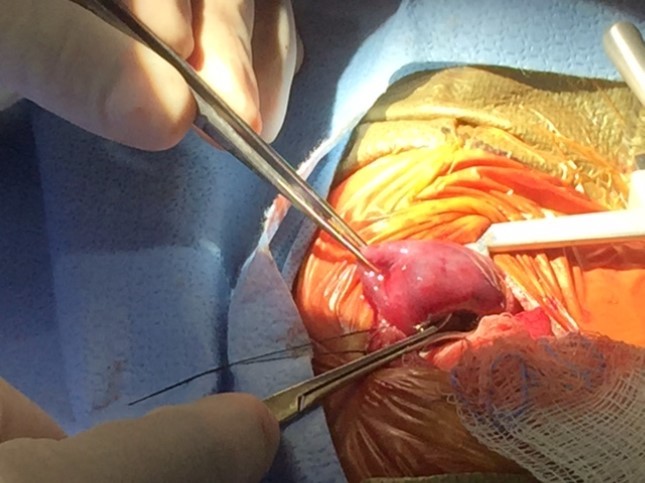

Twin B underwent surgical intervention on day of life3. A large ELS was removed by thoracotomy after ligation of the systemic vascular supply Figure 3. Twin A had an uneventful neonatal intensive care unit (NICU) stay. Twin B made a uneventful recovery and was discharged from the NICU after a two week stay. At one year the infant is doing well and has almost caught up with his twin in terms of body weight and milestones.

Figure 3.Post natal thoracotomy showing the CLM with a systemic blood supply being removed sucessfully.